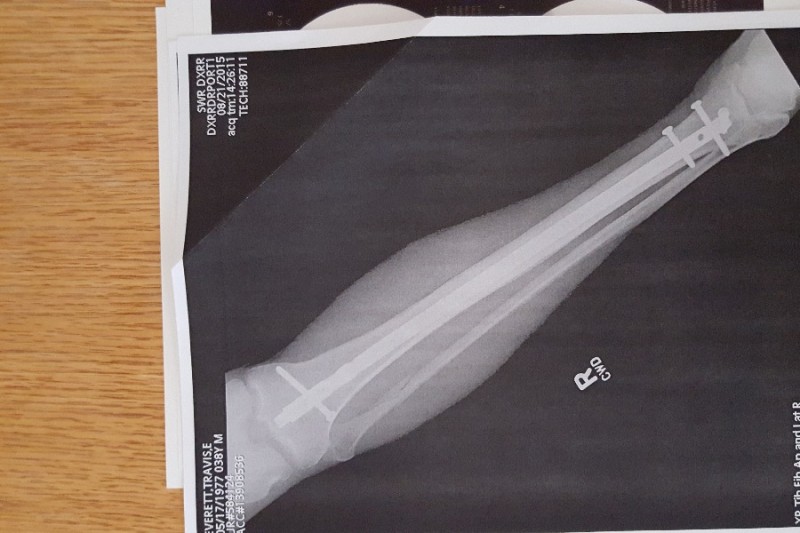

On August 20, 2015 I was out for a motorcycle ride with friends and had an unfortunate accident that broke my right leg in three places. As result of the accident I will not be able to work for at least 12 weeks. I have health insurance but it has a high deductible and out of pocket maximum. I have tried to pay all of my hospital and doctor bills on my own. I have sold off a lot of my "extra stuff" but it’s just not enough to stay afloat. I also have Short Term Disability but it only pays me a fraction of my income, not enough to cover normal household expenses let alone all the extra medical expenses.